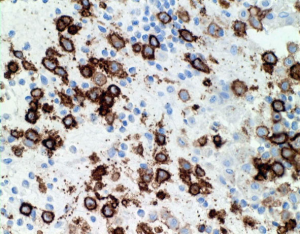

LCHの病理像

頭蓋骨のLCHの病理像です。左はHE染色,右はランゲルハンス細胞に特異性の高いCD1a(specific to dendric Langerhans cells) 染色です。多数のLangerhans cellとともに,組織球,リンパ球,好酸球,多核細胞など多彩な細胞浸潤があります。これは活動性のLCHの病巣から摘出したものです。

自然緩解して収まった病巣を生検術で摘出しても,このような典型的な病理像がなくて慢性炎症像がみられるだけのことがあります。その場合は確定診断がつきません。

CDa-1染色です